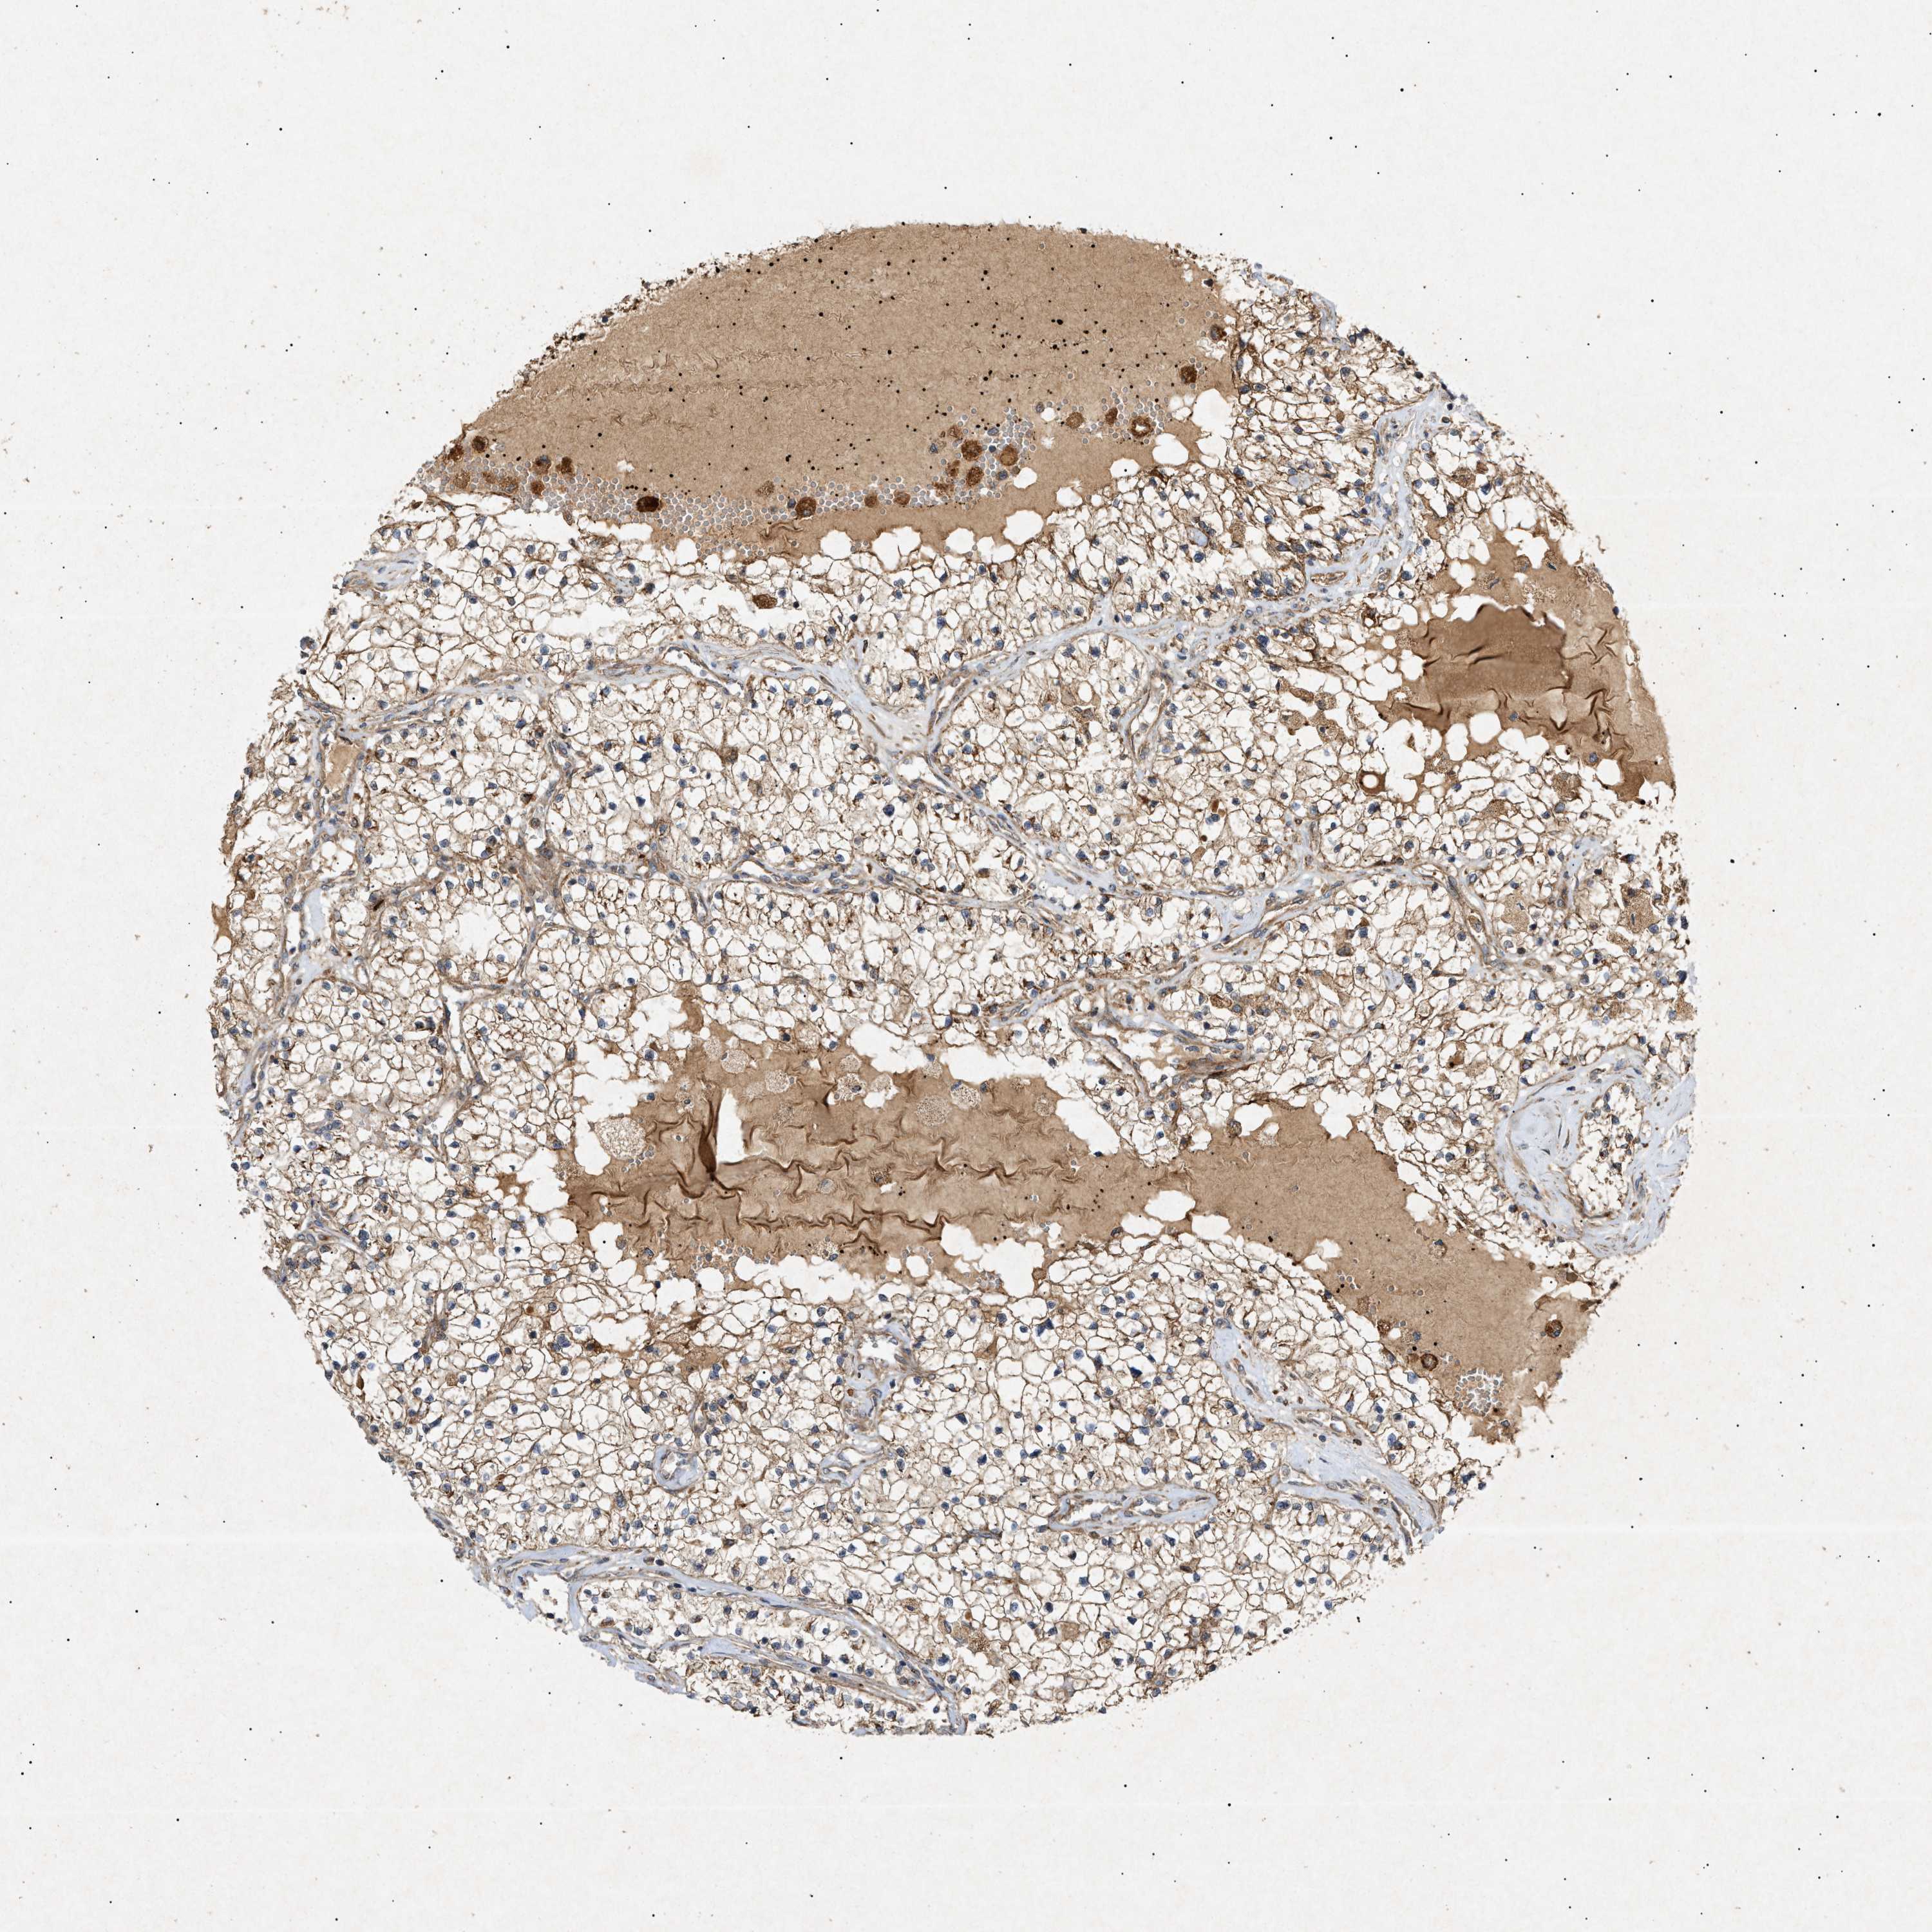

KIDNEY RENAL CLEAR CELL CARCINOMA (VALIDATION) - Interactive survival scatter ploti

The Survival Scatter plot shows the clinical status (i.e. dead or alive) for all individuals in the patient cohort, based on the same data that underlies the corresponding Kaplan-Meier plots. Patients that are alive at last time for follow-up are shown in blue and patients who have died during the study are shown in red.

The x-axis shows the expression levels (FPKM) of the investigated gene in the tumor tissue at the time of diagnosis. The y-axis shows the follow-up time after diagnosis (years). Both axes are complimented with kernel density curves demonstrating the data density over the axes. The top density plot shows the expression levels (FPKM) distribution among dead (red) and alive patients (blue). The right density plot shows the data density of the survived years of dead patients with high and low expression levels respectively, stratified using the cutoff indicated by the vertical dashed line through the Survival Scatter plot. This cutoff is automatically defined based on the FPKM cutoff that minimizes the p-score. The cutoff can be changed by dragging the vertical line or by entering a cutoff value in the square labeled "Current cut-off".

Under the Survival Scatter plot the p-score landscape (black curve; left axis) is shown together with dead median separation (red curve; right axis). Dead median separation is the difference in median mRNA expression between patients who have died with high and low expression, respectively. It is calculated as follows: median FPKM expression of dead patients with high expression - median FPKM expression of dead patients with low expression. This is intended to aid the user in visually exploring custom cutoffs and the associated p-scores and dead median separation.

Individual patient data is displayed and can be filtered by clicking on one or more of the category buttons on the top of the page. Categories describing expression level and patient information include: high, low, alive, dead, female, male and tumor stages. The scale of the x-axis can be toggled between linear and log-scale by clicking on the "x log" button. Mouse-over function shows TCGA ID, patient information and mRNA expression (FPKM) for each patient.

& Survival analysisi

Kaplan-Meier plots summarize results from analysis of correlation between mRNA expression level and patient survival. Patients were divided based on level of expression into one of the two groups "low" (under cut off) or "high" (over cut off). X-axis shows time for survival (years) and y-axis shows the probability of survival, where 1.0 corresponds to 100 percent.

MTCH1 is validated prognostic, high expression is favorable in Kidney Renal Clear Cell Carcinoma (validation)

Best expression cut offi

Based on the FPKM value of each gene, patients were classified into two groups and association between prognosis (survival) and gene expression (FPKM) was examined. The best expression cut-off refers the FPKM value that yields maximal difference with regard to survival between the two groups at the lowest log-rank P-value. Best expression cut-off was selected based on survival analysis .

When clicking on this number, the vertical dashed line indicating cut-off, the interactive survival plot, and the Kaplan-Meier curve will be adjusted to show results based on the best expression cut-off.

: 143.1

TCGA RNA samplesi

RNA-seq data is reported as average FPKM (number Fragments Per Kilobase of exon per Million reads), generated by the The Cancer Genome Atlas (TCGA) .

Normal distribution across the dataset is visualized with box plots, shown as median and 25th and 75th percentiles. Points are displayed as outliers if they are above or below 1.5 times the interquartile range. FPKM values of the individual samples are presented next to the box plot.

Average pTPM 164.3

Number of samples 100